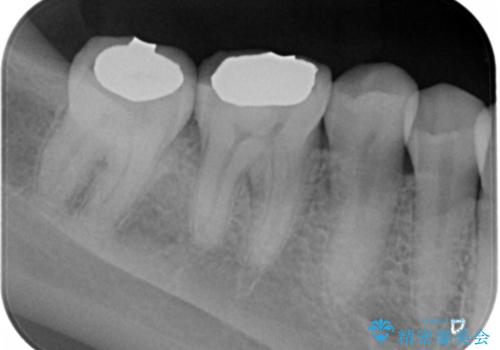

- 奥歯がしみるとのことで来院。レントゲンを確認したところ虫歯はなかったが、歯の咬む面がすり減っていました。

歯ぎしりがとても強い方で、セラミックの詰め物だと割れてしまう可能性があることを伝えたところ、なるべく割れにくいものが良いとのことでしたので、ゴールドインレーによる治療を行いました。

- ゴールドインレー 7.7万円費用は治療当時の料金となります